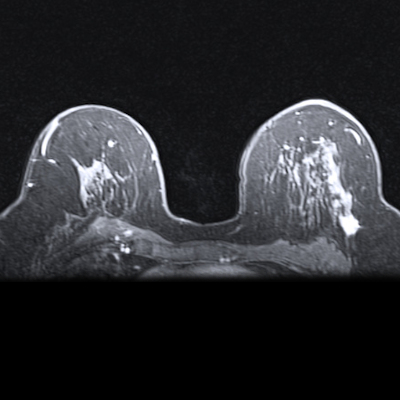

This has prompted a research team from Vienna and Rome to produce an authoritative and comprehensive article on MRI of the vulvar. It was published on Monday, and the authors have kindly agreed to share four sets of clinical images with us. Please take a look at today's top story.

In another intriguing study published this week, the authors reported that women with inherited pathological variants who discuss their breast cancer risk with their doctors had more consistent MRI uptake than women with lower estimated risk.